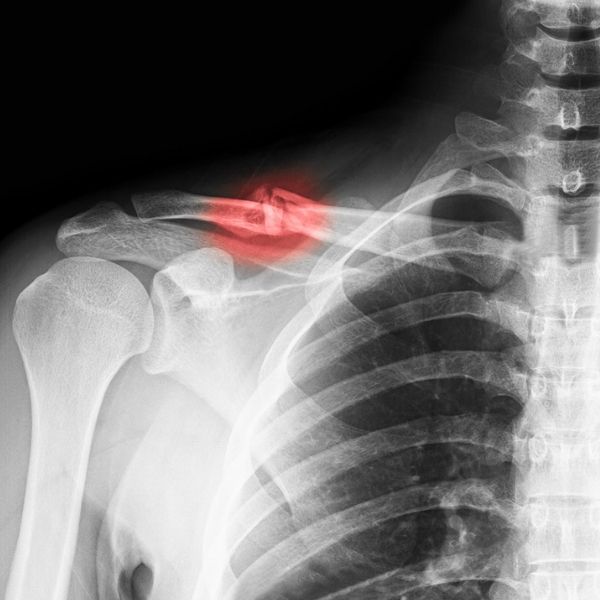

Fractures

Fractures in the shoulder occur for a variety of reasons, but typically from a fall onto the shoulder itself. Fractures can occur in seniors also due to osteoporosis (thinning and weakening of bone).

The goal with fracture management is to provide a safe position for the bone to heal (typically around 8 weeks), while maintaining range of motion. As the bone heals, strengthening can begin and rehabilitation back to normal activities is progressed.

At times surgery may be needed to hold the bone together with plates or screws. This stabilizes the bone, but does disrupt muscles and leads to more weakness in the shoulder muscles. Physical therapy is very much needed after this to restore normal range of motion and strength to the shoulder. Recovery times can vary, but traditionally take 12-16 weeks.